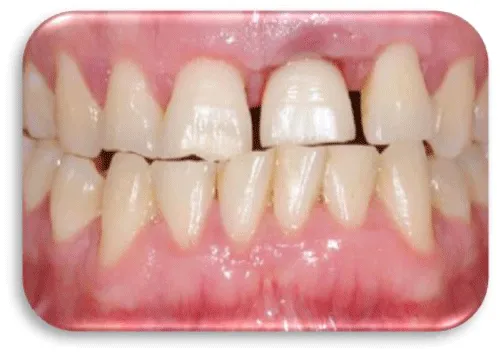

In peri-implant mucositis, the marginal gingiva in lightly bleeding bleeds. Gingiva is hyperemic and oedematous. The patient feels discomfort, mastication of food also leads to bleeding (Figure 4) [16].

The third clinical cases was a 47 year old male patient with a dental implant [21], placed in the frontal region of the maxilla. More precisely, implant compensates for the naturally lost central left incision. After three months of dental implant placement, the patient began to complain of pain coming from the area where the dental implant was placed. The marginal gingiva in that region was oedematous and hyperemic, and blood was drained during the process of probing. The peri-implant mucositis was detected. On the figures 21-25 the situation before the surgery treatment was seen.